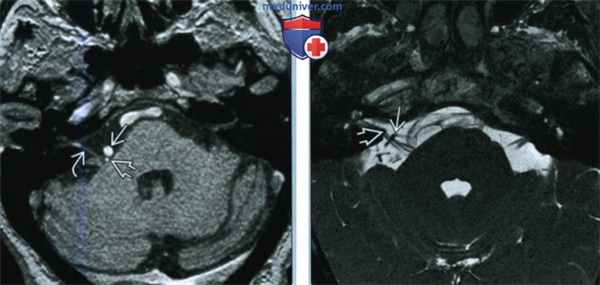

По данным МРТ головного мозга визуализировано нетипичное предлежание сразу трех внутричерепных сосудов к корешку левого лицевого нерва в зоне его выхода из вещества моста: колена базилярной, петли ветви верхней мозжечковой и передней нижней мозжечковой артерий (рис. 1). Значительно чаще при гемифациальном спазме отмечается компрессия корешка лицевого нерва только одним сосудом. По данным электронейромиографии при стимуляции височной ветви левого лицевого нерва получен прямой М-ответ от лобной мышцы (переднее брюшко лобно-затылочной мышцы) и патологический ответ от подбородочной мышцы с увеличенной латентностью и амплитудой до 15% от амплитуды прямого М-ответа.

Рис. 1. МРТ головного мозга в аксиальной и коронарной проекциях: отмечается близкое расположение петли базилярной, петли ветви верхней мозжечковой и передней нижней мозжечковой артерий к корешку левого лицевого нерва в зоне его выхода из вещества моста.